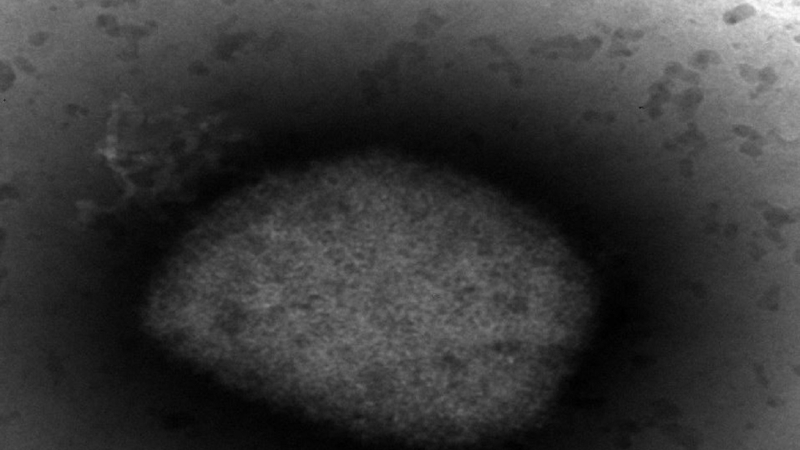

España obtiene la secuencia completa del genoma del virus causante de la viruela del mono. Han sido investigadores del Instituto de Salud Carlos III, dependiente del Ministerio de Sanidad, los que han conseguido un primer borrador que viene a confirmar que la variedad causante del brote dado en nuestro país es la de África Occidental, menos grave.

El análisis genómico de muestras de 23 pacientes o lo que es lo mismo, la secuencia, ha alcanzado asimismo una cobertura del 100% de los 190.000 pares de bases de genoma del virus. Esto abre la posibilidad de emprender estudios filogenéticos más avanzados que permiten conseguir información adicional y avanzada acerca del comportamiento, el origen y la circulación del virus.